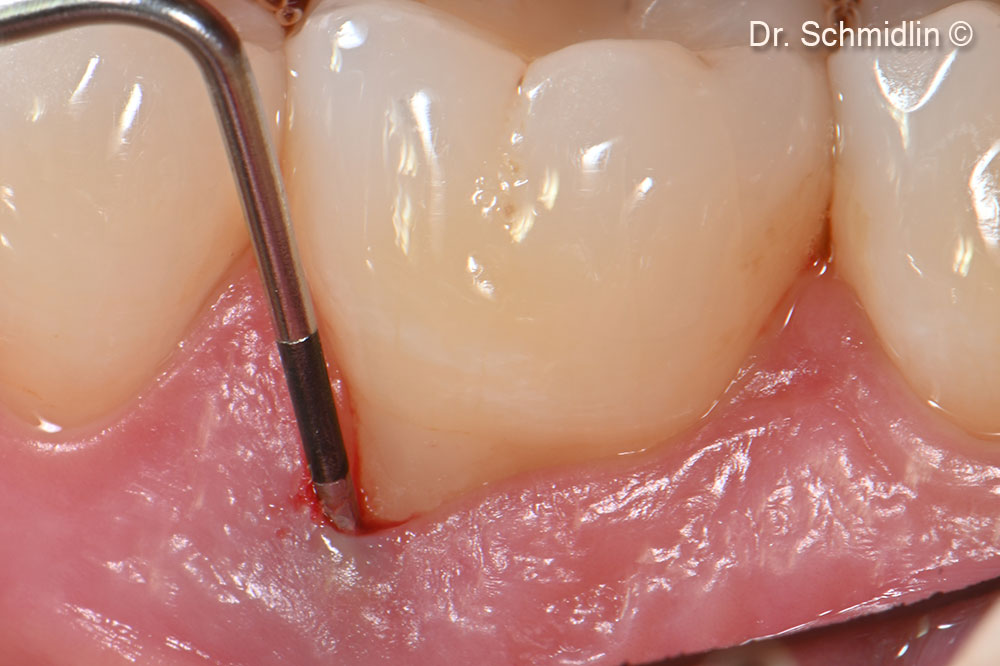

Periodontal probing of the affected site